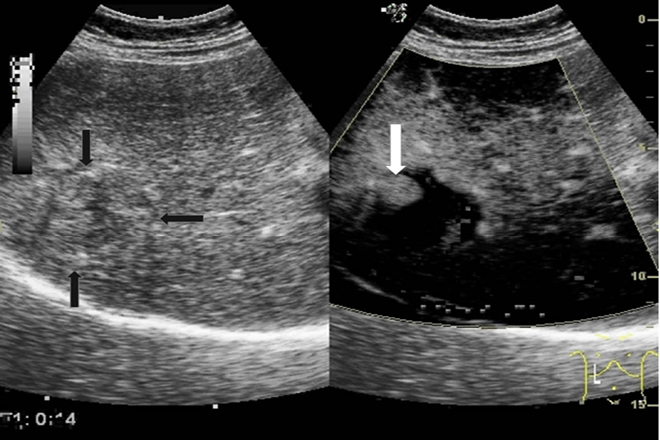

Ultrasonido con contraste de masas Hepáticas

El ultrasonido con contraste (en inglés, Contrast-enhaced Ultrasonography, CEUS) de hígado es un método usado para evaluar masas hepáticas. Ofrece una excelente resolución espacial y de contraste y puede mostrar cierta vascularidad con la técnica doppler, tiene limitaciones para caracterizar la vascularidad de las lesiones